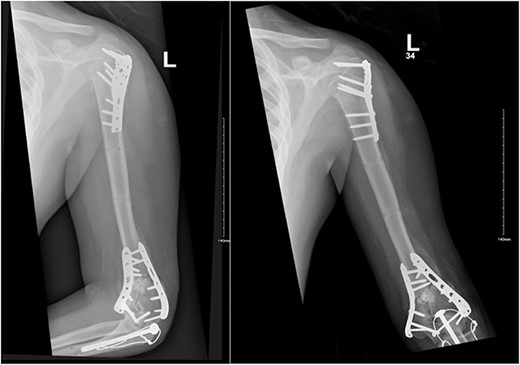

Upon arrival the patient underwent exploratory laparotomy followed by irrigation and debridement of both femur and humerus and application of external fixators (Fig. 2). The patient was admitted to the intensive care unit (ICU). Two days later, the patient underwent open reduction and internal fixation of both proximal and distal humerus (Fig. 3).

Anteroposterior (AP) view of the left humerus and elbow after Ex-fix application.